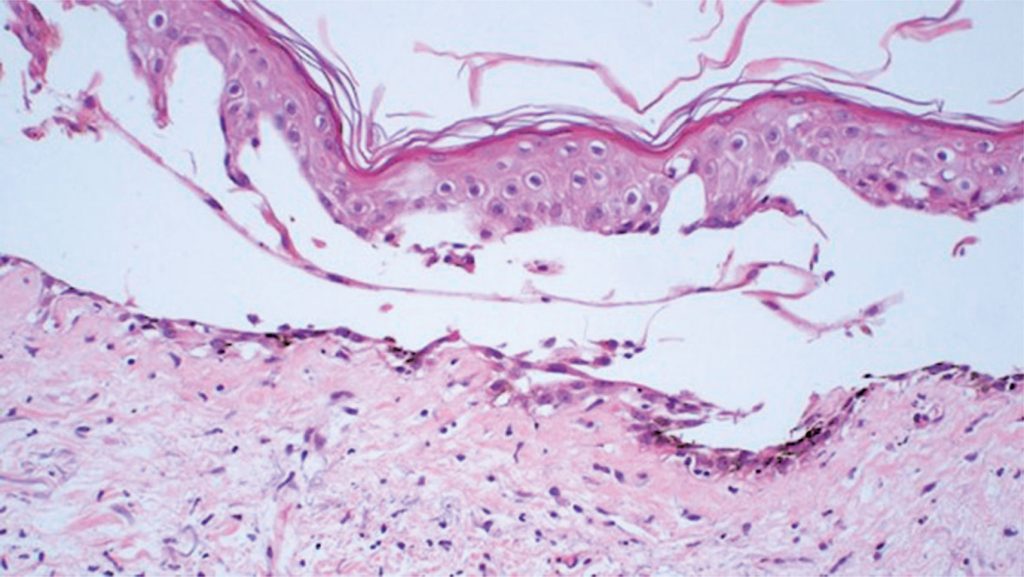

Azacitidine-induced bullous pemphigoid-like localized toxic reaction

Azacitidine is a hypomethylating agent recommended for the treatment of patients with high-risk myelodysplastic syndromes. Here, we report the case of a patient with myelodysplastic syndrome who was not eligible for allogeneic stem cell transplantation (allo-SCT) and presented with a rare and previously unreported cutaneous side effect after the use of subcutaneous azacitidine. We propose that changing the route of azacitidine administration from subcutaneous to intravenous could potentially decrease the occurrence of bullous pemphigoid-like localized toxic reactions in some patients.